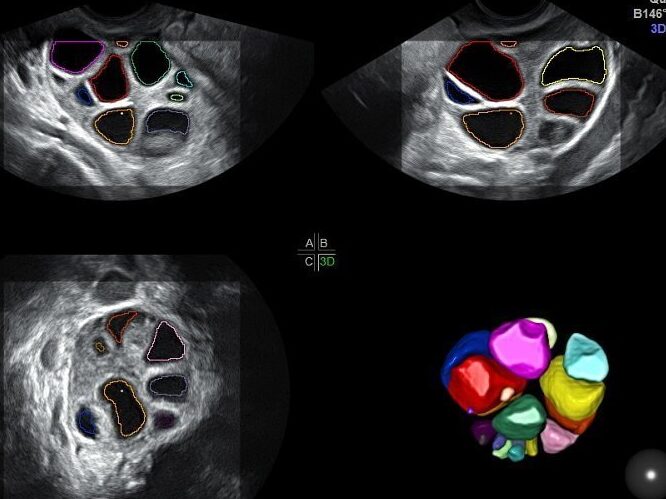

Ecografía para el recuento de folículos antrales

Una de las pruebas más comunes para evaluar la reserva ovárica es la ecografía para el recuento de folículos antrales. Esta prueba se realiza mediante una ecografía transvaginal, en la que se cuenta el número de folículos antrales presentes en los ovarios. Los folículos antrales son pequeñas estructuras que contienen los óvulos en desarrollo. Cuanto mayor sea el número de folículos antrales, mayor será la reserva ovárica.